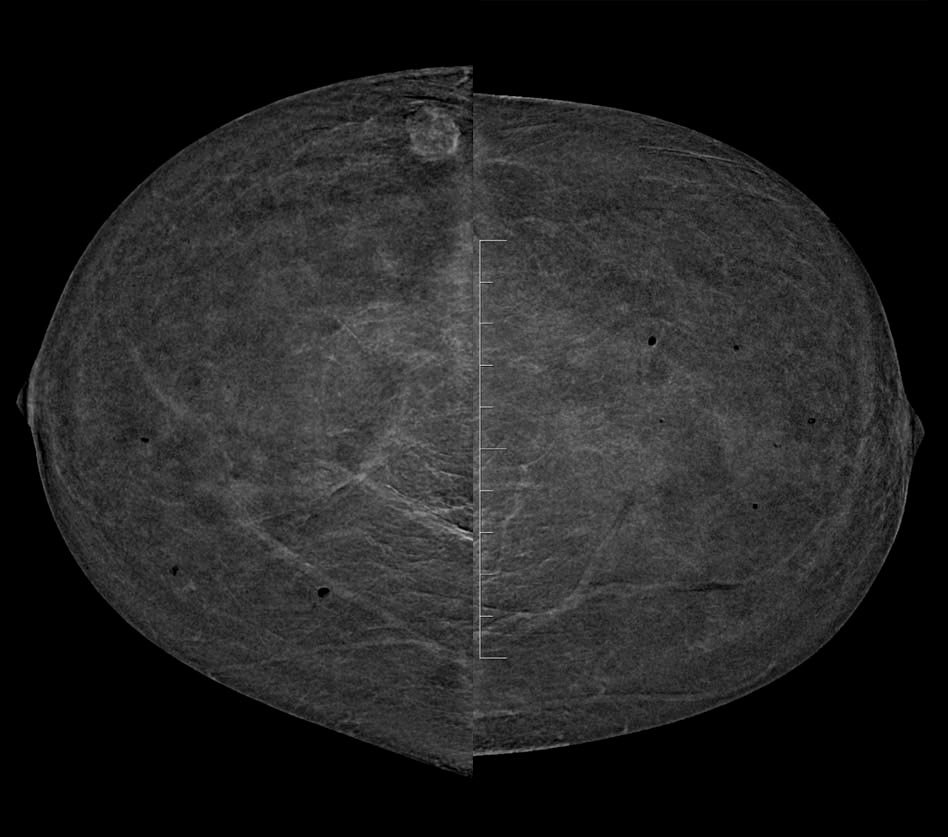

- Control previo en el PPDCMA (Programa de Prevención del Cáncer de Mama en Aragón) en 2019 normal. Control actual en las imágenes.

- A. BI-RADS 0. Hay que completar estudio con RM con contraste.

- B. BI-RADS 1. No hay que hacer nada porque el nódulo tiene aspecto benigno.

- C. BI-RADS 4. Haremos biopsia con aguja gruesa (BAG) del nódulo.

- D. BI-RADS 2. Haremos punción con aguja fina (PAAF) del nódulo.

- E- BI-RADS 3. Control con ecografia mamaria en 6 meses.